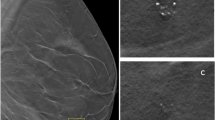

The selective and iterative method for performance level estimation (SIMPLE) algorithm for label fusion was modified with a weight map given by an expert that indicates the importance of each region in the evaluation of segmentation results. Voxel-based weights specified by an expert when performing the label fusion step in atlas-based segmentation were introduced into the modified SIMPLE algorithm. These weights incorporate expert knowledge on accuracy requirements in different regions of a segmentation. Using this knowledge, segmentation accuracy in regions known to be important can be improved by sacrificing segmentation accuracy in less important regions. Contextual information such as the presence of vulnerable tissue is then used in the segmentation process. This method using weight maps to fine-tune the result of multi-atlas-based segmentation was tested using a set of 146 atlas images consisting of an MR image of the lower abdomen and a prostate segmentation. Each image served as a target in a set of leave-one-out experiments. These experiments were repeated for a weight map derived from the clinical practice in our hospital.

The segmentation accuracy increased 6 % in regions that border vulnerable tissue using expert-specified voxel-based weight maps. This was achieved at the cost of a 4 % decrease in accuracy in less clinically relevant regions.